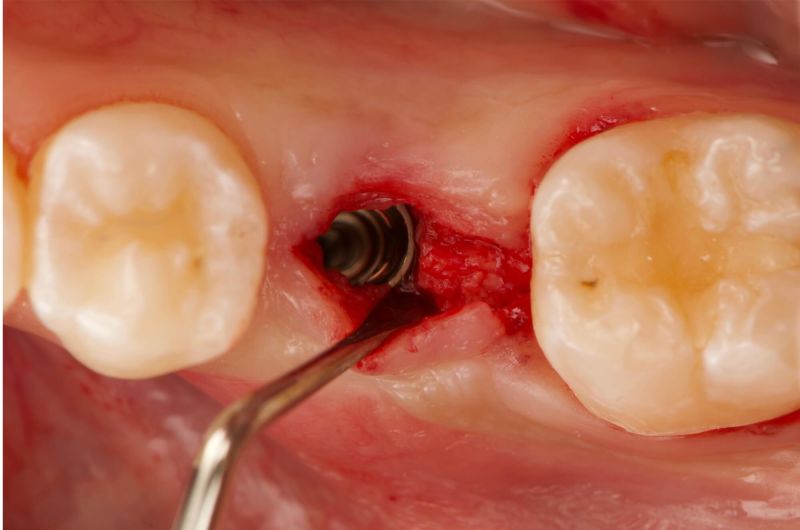

Atraumatic Extraction, Bone Grafting and Implant Placement

Our periodontist removed this damaged tooth and added bone to preserve the area. Four months later, a dental implant was carefully placed followed by a new tooth for optimal chewing and appearance.